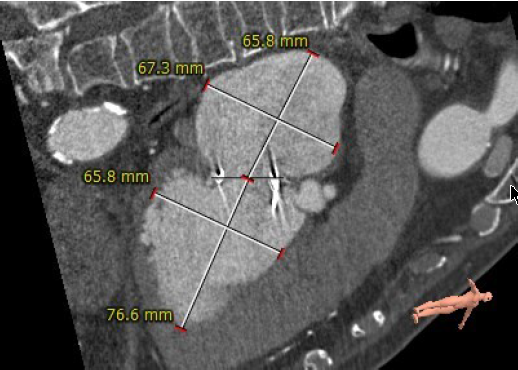

左房及左室内径

主动脉与生物瓣轴夹角76°

左室与生物瓣轴夹角145°